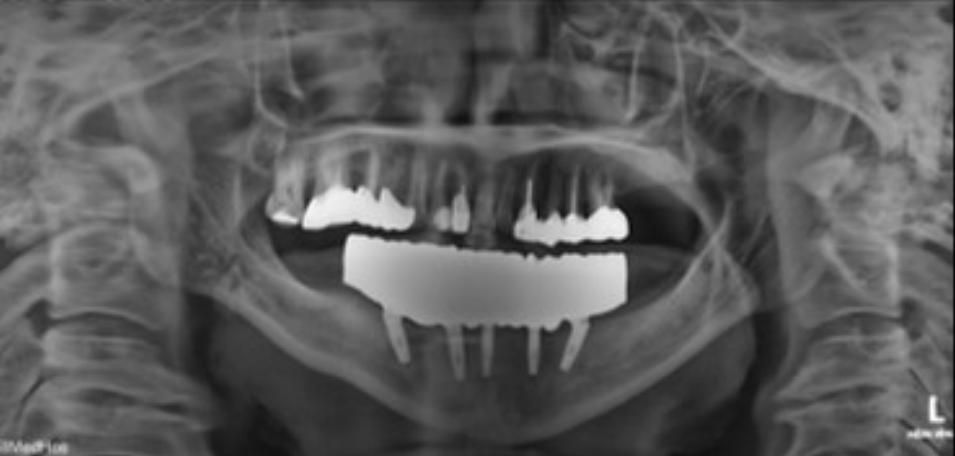

Fig. 3.

The lower jaw is edentulous with severe alveolar bone loss.

jkda-2025-63-7-001f3.jpg

본 증례는 44세 여환으로, 하악 의치가 계속 탈락하여 재제작을 원한다는 주소로 내원하였다. 상악은 고정성 수복물, 그리고 하악은 총의치를 착용 중이었고 하악 양측 구치부의 심한 골 흡수로 인해 유지력 소실로 불편감을 호소하였다. 3개월 전 하악 양측 견치를 발거한 이후로 하악 국소의치를 총의치로 전환하였고, 총의치는 구치부의 심한 교합면 마모와 의치의 후방부가 후구치 삼각 융기를 피개하지 않는 형태였다. 전신 병력으로는 지적장애 및 골관절염으로 약 2개월 간 약물 복용 중이었다. 상악 우측 제1대구치와 제2대구치, 제1소구치 그리고 제2소구치는 우식이 진행된 상태였고, 우측 제2소구치와 우측 제1대구치는 근관치료가 완료된 후 수복되지 않은 상태였다. 상악 좌측 제1소구치와 제2소구치, 그리고 제1대구치 수복물 하방으로 이차 우식이 진행된 상태였고, 전체적으로 교합평면이 균일하지 않은 형태였다(Figs. 1-3).